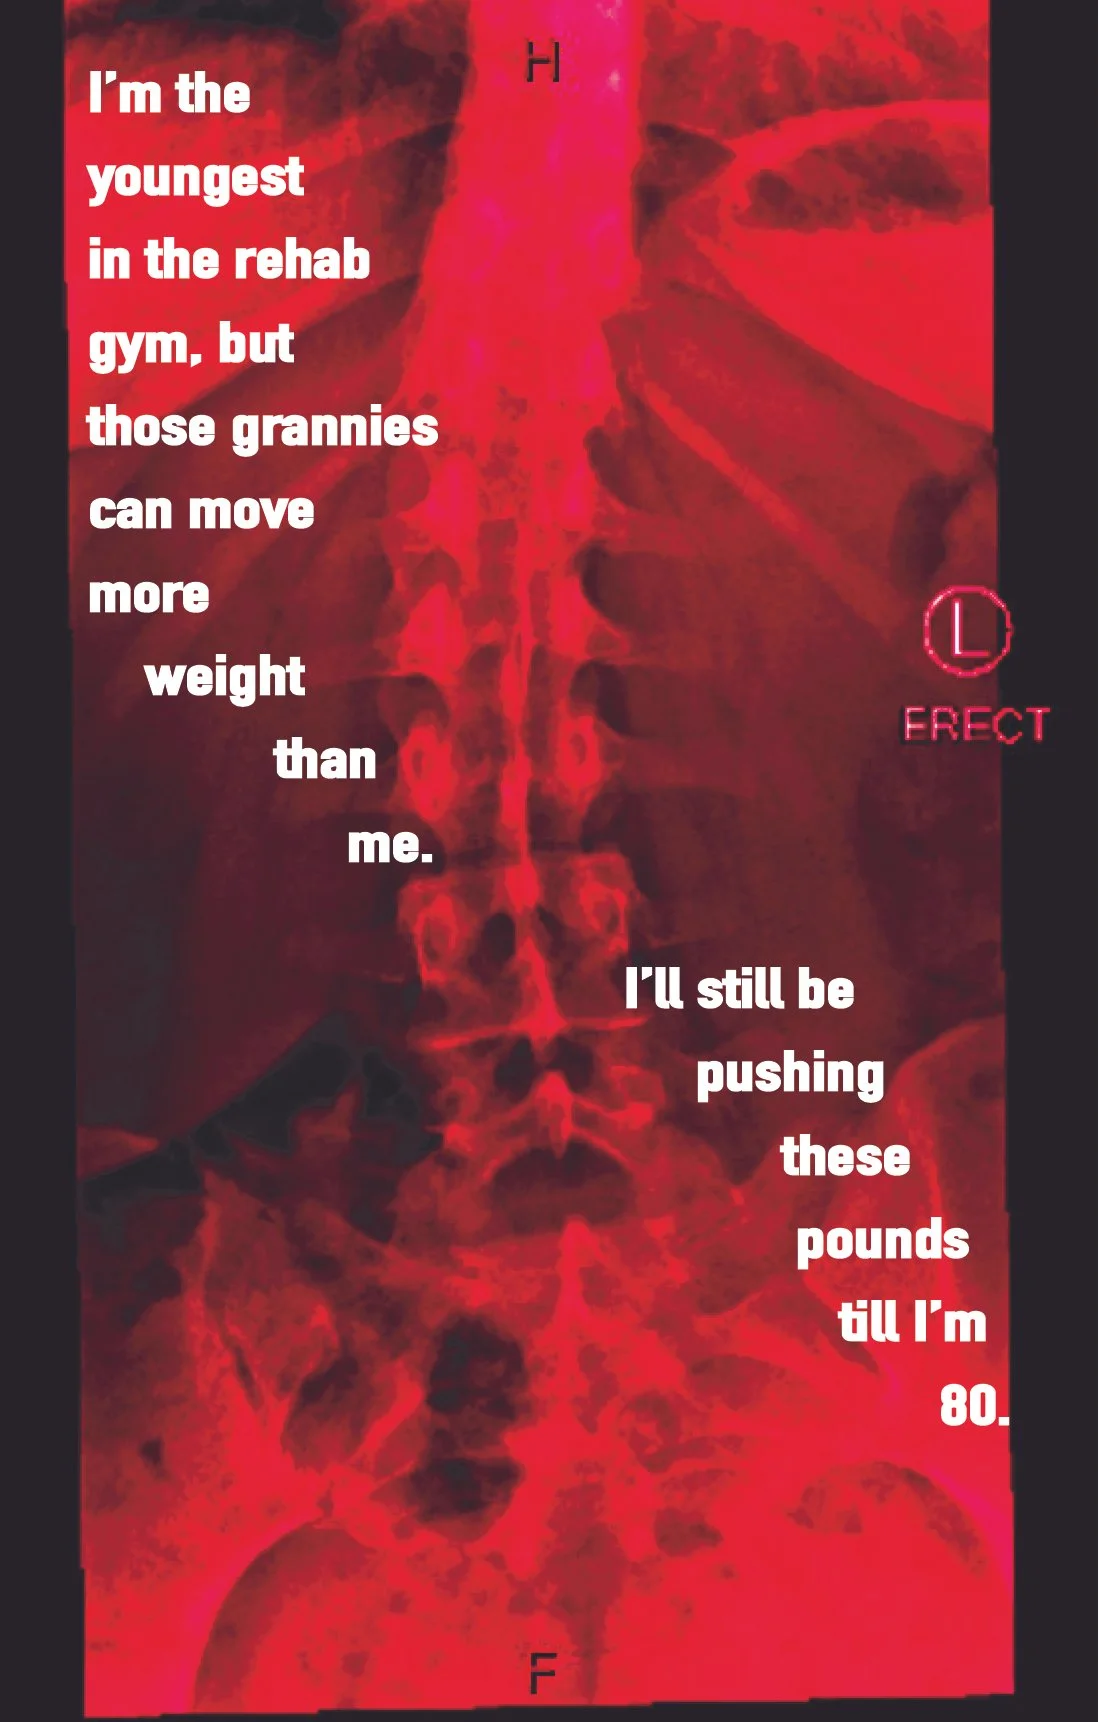

Confessions of a Bad-Backed Young Masc